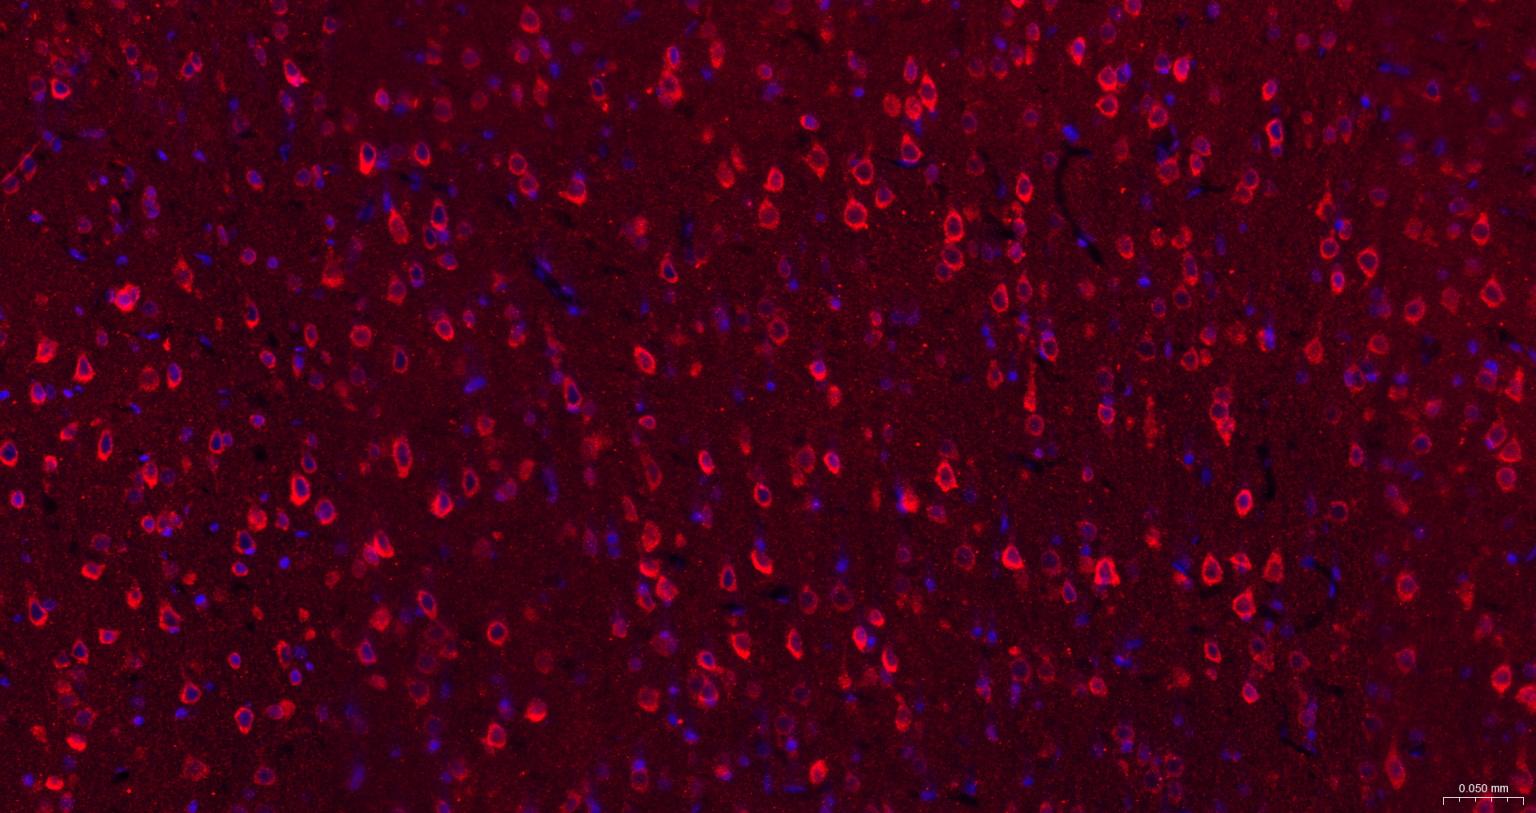

| IHC-P | Human, Mouse, Rat, Rabbit, Pig, Cow, Dog, Horse | 1:100-500 | |

| IHC-F | Human, Mouse, Rat, Rabbit, Pig, Cow, Dog, Horse | 1:100-500 | |

| IF | Human, Mouse, Rat | Rabbit, Pig, Cow, Dog, Horse | 1:100-500 |

交叉反应: Human, Mouse, Rat (predicted: Rabbit, Pig, Cow, Dog, Horse)